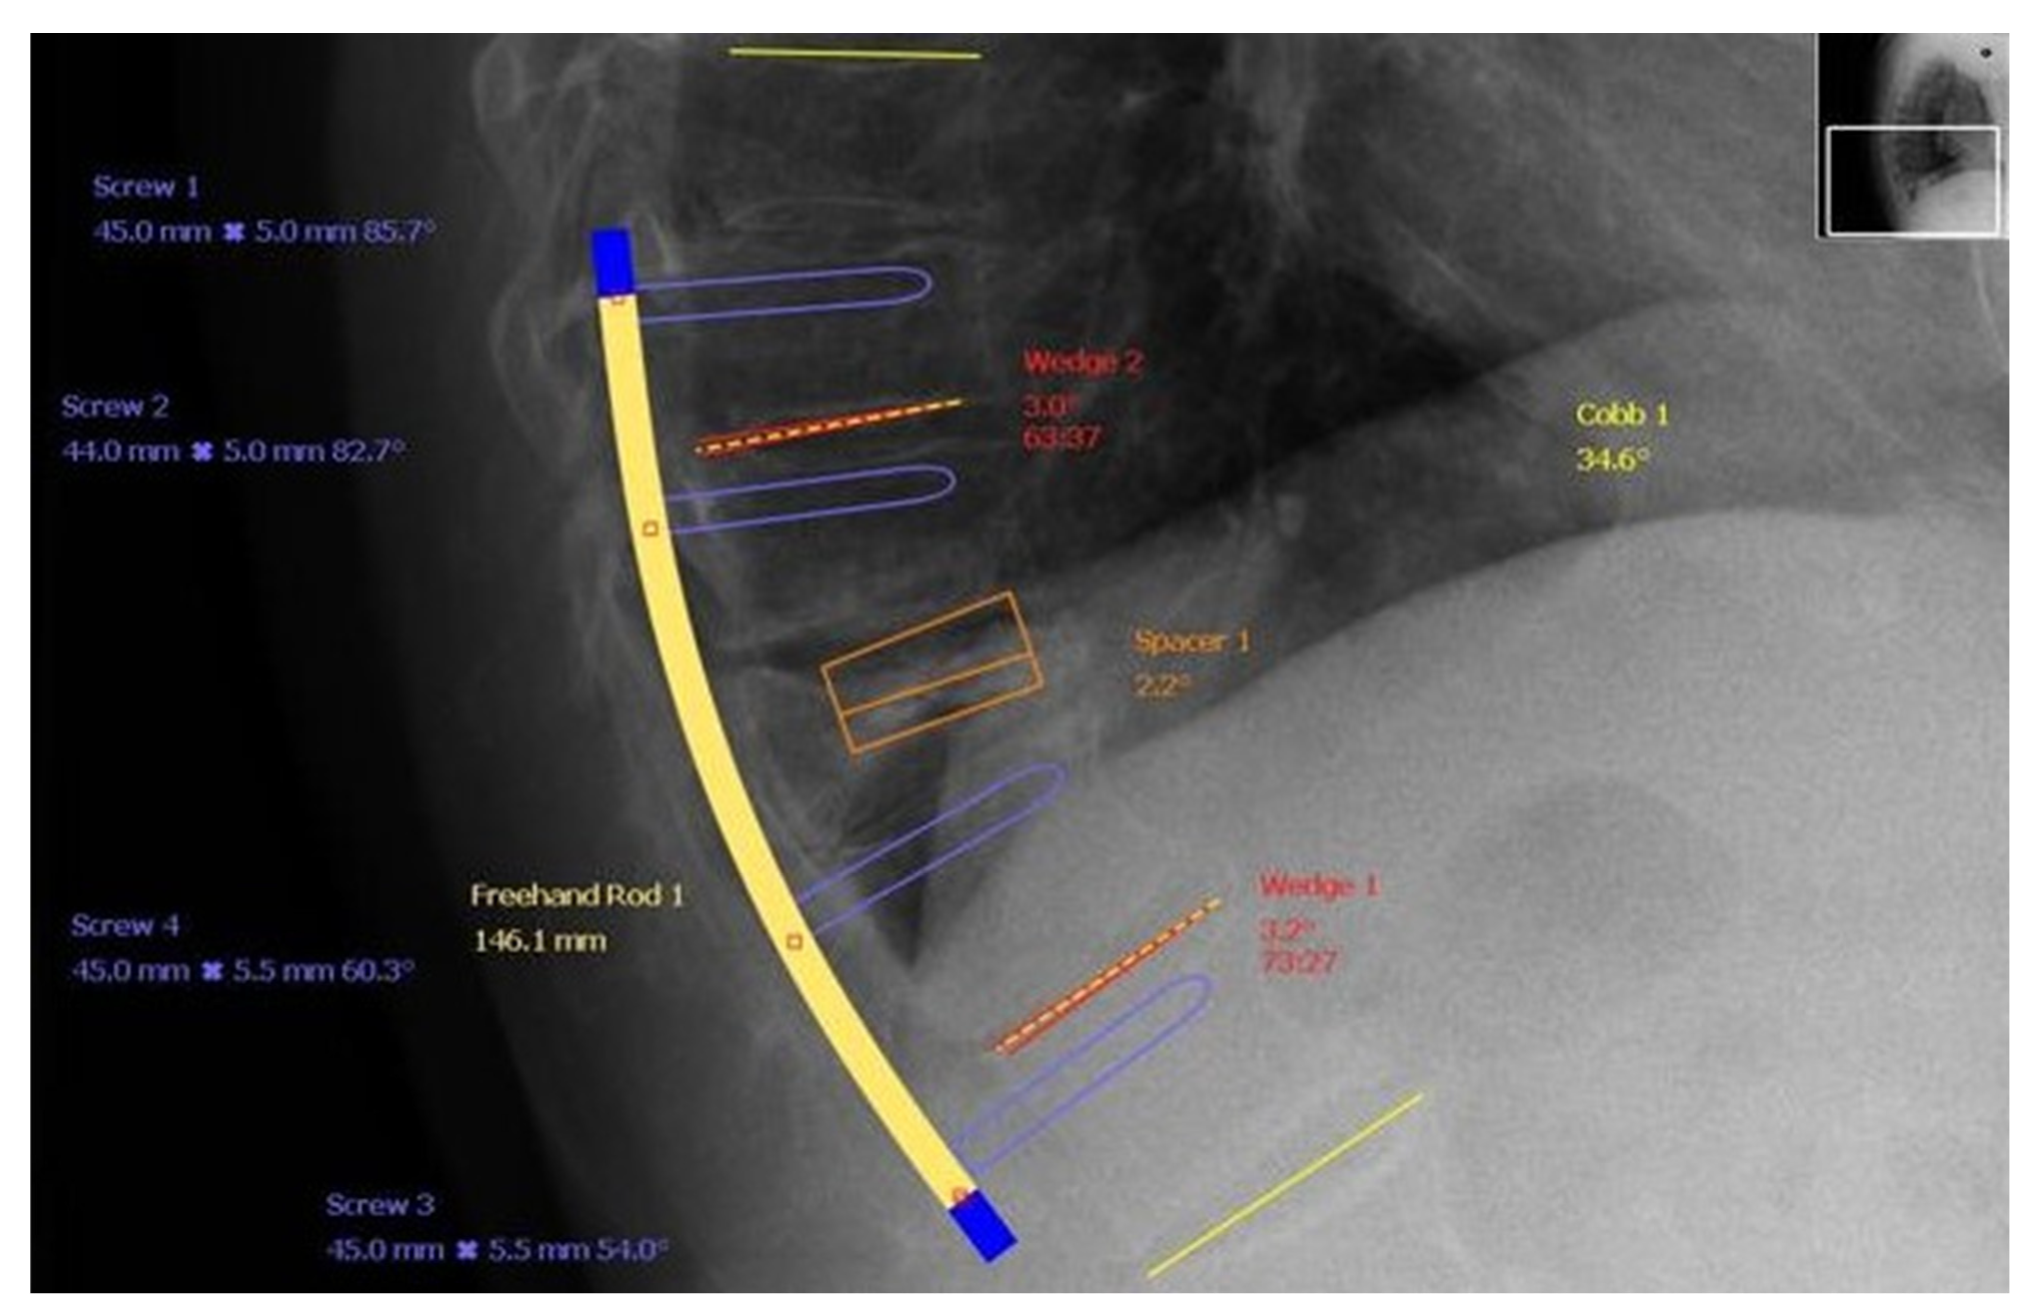

- Adamska, O.; Modzelewski, K.; Stolarczyk, A.; Kseniuk, J. Delayed posttraumatic vertebral body collapse “Kummell disease”. Med. Case Rep. Study Protoc. 2021, 2, e0092. [Google Scholar] [CrossRef]